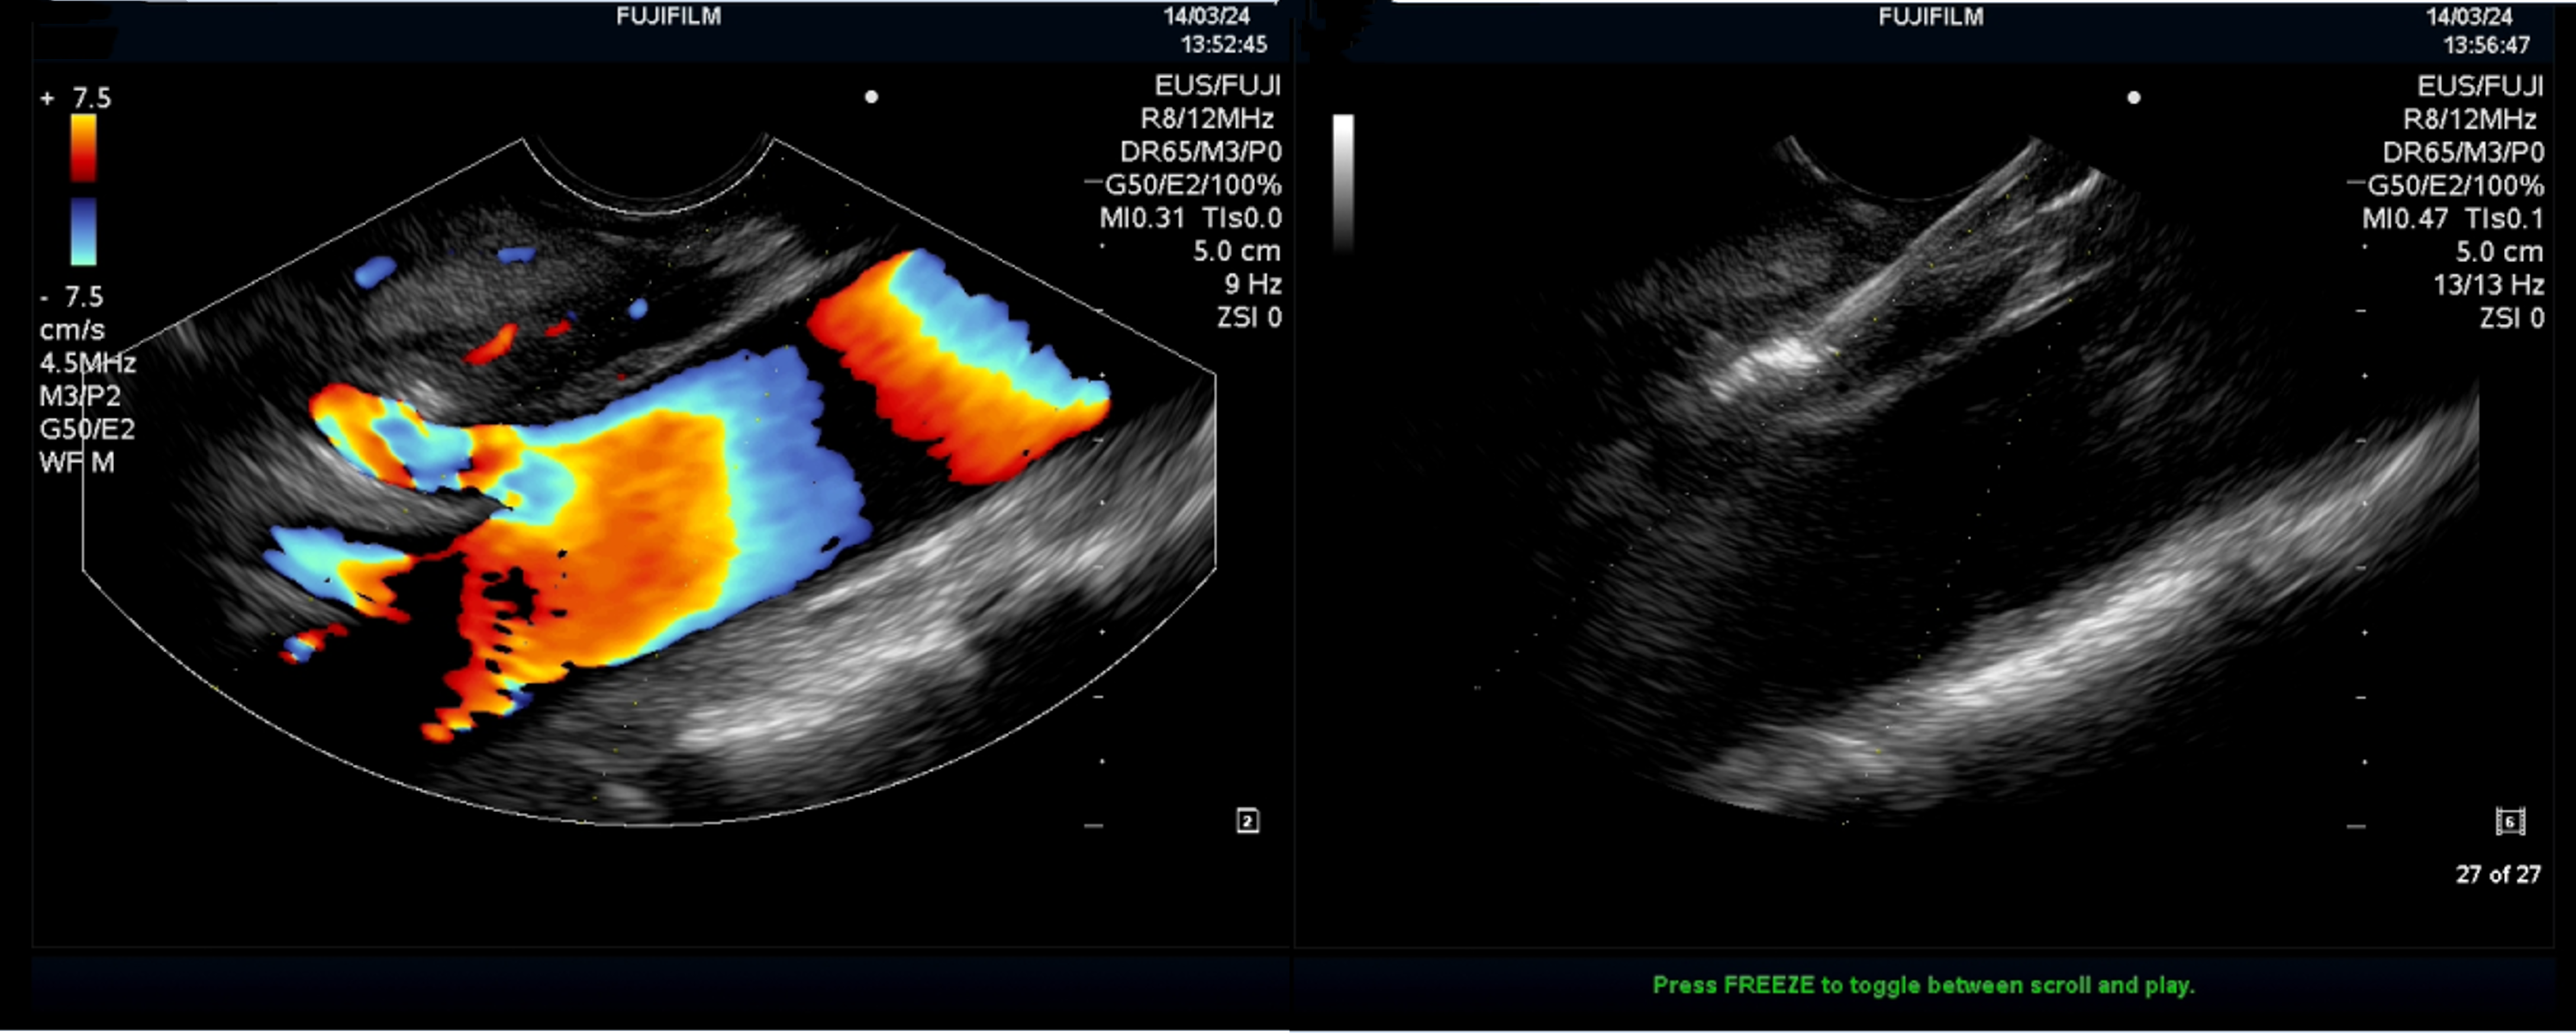

超声内镜定位腹腔神经节(左)及穿刺注射无水乙醇(右)治疗顽固性腹痛

手术当天,在超声内镜的引导下,黄永辉准确定位腹主动脉与腹腔干夹角的腹腔神经丛,通过穿刺注入2%利多卡因5ml和15ml无水乙醇,使神经节毁损而达到止痛作用,仅仅用时十分钟手术便顺利结束。